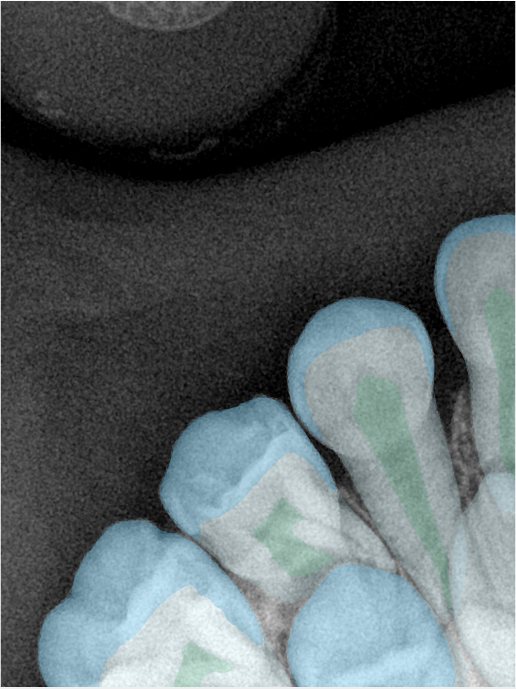

CR/DR 牙齿分割阶段记录

当前进展

- 完成了 CR/DR 牙齿相关分割训练

- 当前结果已经达到阶段预期,但仍有细节问题需要继续处理

相关测试

遇到的问题

- 训练过程中出现过 mask 下移问题

- 部分结果会出现 box 填充异常

- mask 边缘仍然有比较明显的锯齿感

参考

第二版算法问题测试